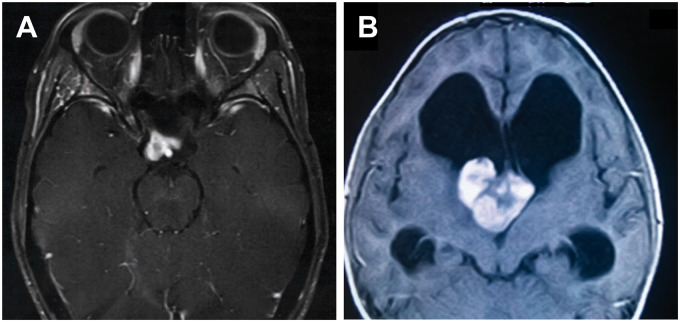

FIGURE 1.

間腦神經(jīng)膠質(zhì)瘤的放射學(xué)特征。(A) T1加權(quán)磁共振成像(MRI)顯示視交叉和右側(cè)視神經(jīng)受累,可見一對比增強的部分囊性腫塊。(B) T1加權(quán)MRI顯示第三腦室前部可見一巨大、分葉狀、對比增強明顯的腫塊。注意側(cè)腦室明顯梗阻性腦積水。